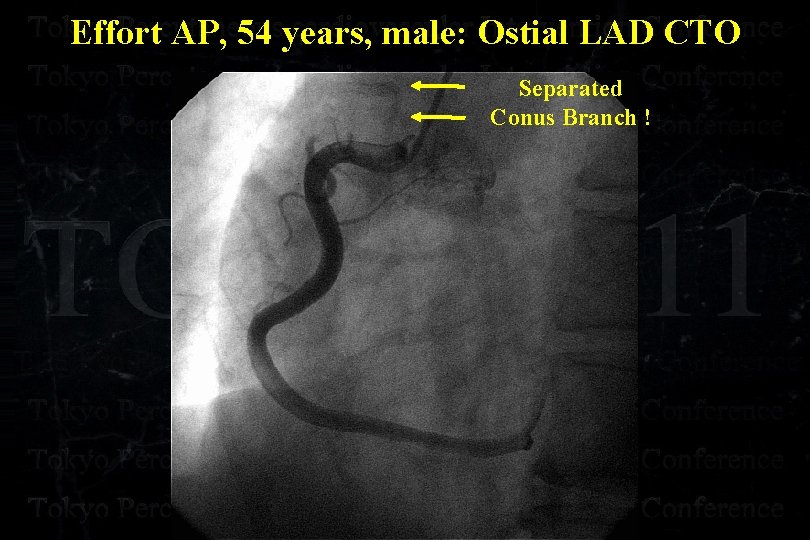

Effort AP, 54 years, male: Ostial LAD CTO

Effort AP, 54 years, male: Ostial LAD CTO

Effort AP, 54 years, male: Ostial LAD CTO

Effort AP, 54 years, male: Ostial LAD CTO

Effort AP, 54 years, male: Ostial LAD CTO

Effort AP, 54 years, male: Ostial LAD CTO

Effort AP, 54 years, male: Ostial LAD CTO Separated Conus Branch !